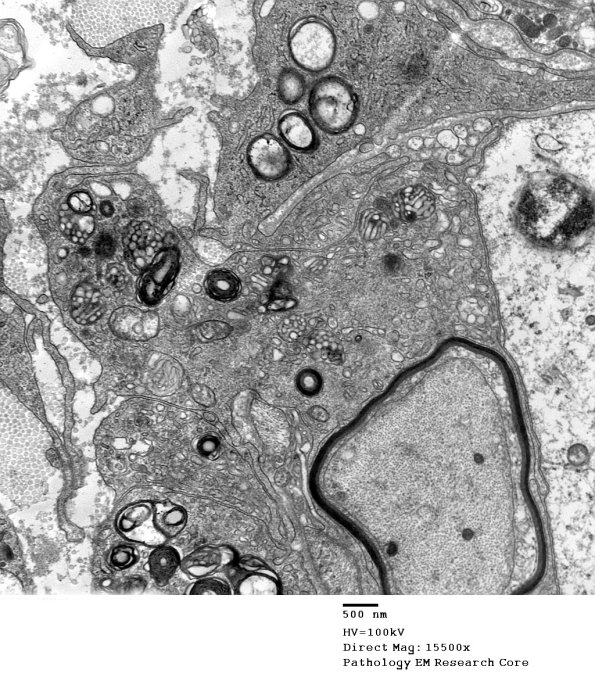

Higher magnification of image #1G2A. (electron micrograph)

1G2B CIDP (Case 1)_031 - Copy